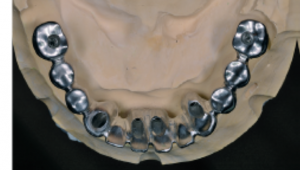

d. Estructura protésica definitiva fresada mediante CAD/CAM con orientación precisa de los canales de tornillo angulados.